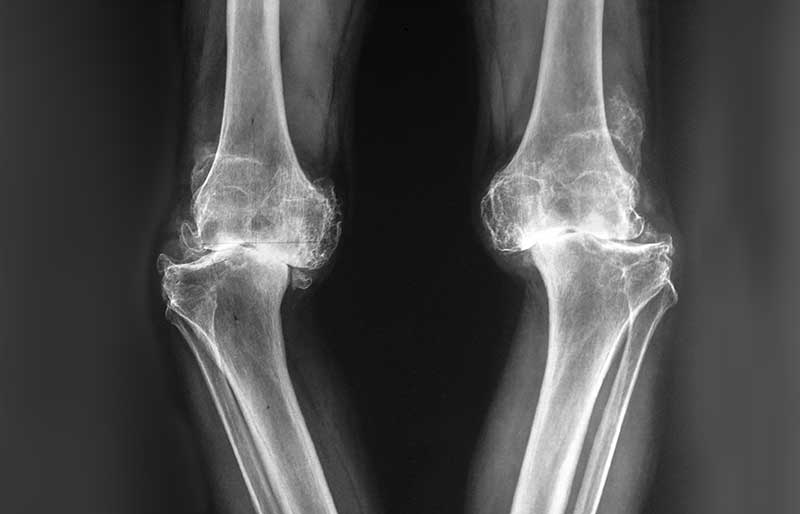

• Pengapuran sendi (osteoartritis) adalah penyakit di mana tulang rawan mengalami kerusakan, penipisan dan akhirnya hilang sama sekali. Penyebab utama pengapuran sendi adalah proses penuaan. Kerusakan tulang rawan sendi menyebabkan sakit sendi. Kerusakan tulang rawan sendi derajad ringan dapat diobati tanpa operasi, tetapi kerusakan sendi derajad berat memerlukan operasi penggantian sendi.